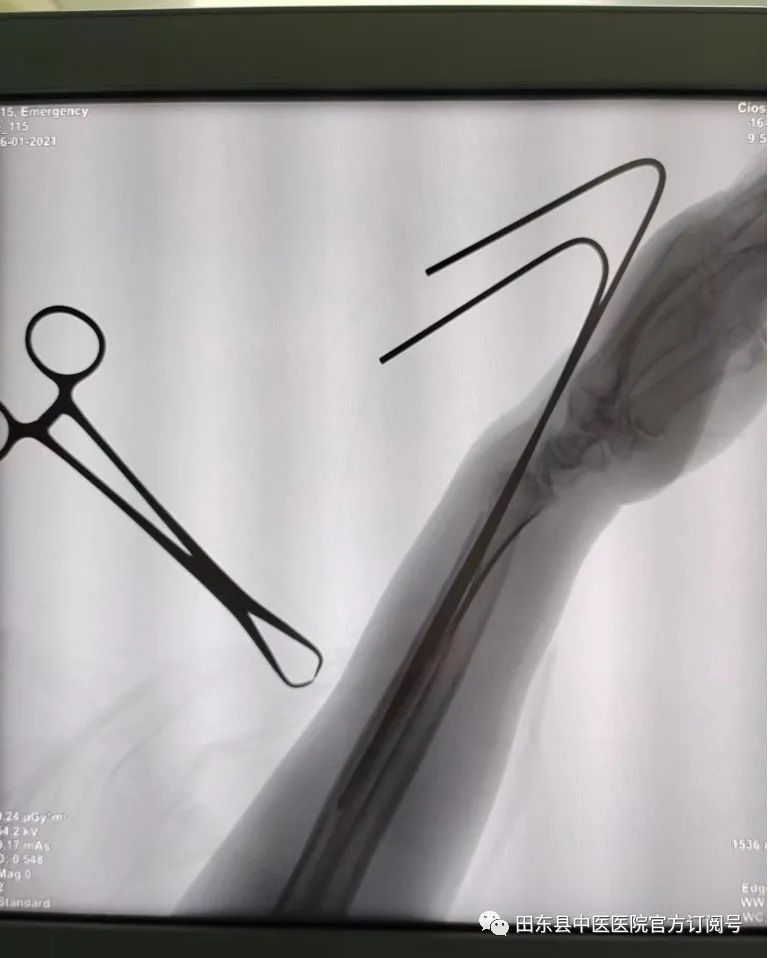

骨伤科一区

闭合复位克氏针内固定治疗桡骨远端骨折